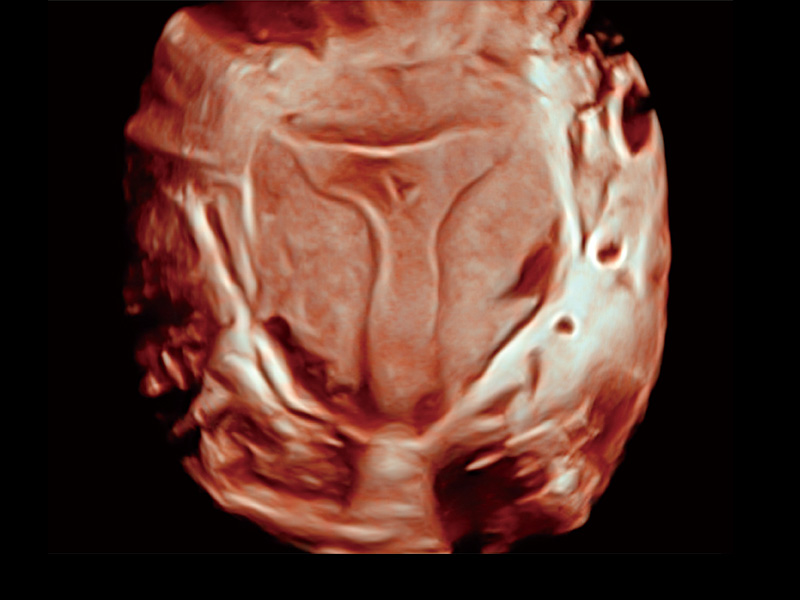

“生育问题”即关系民族复兴,也关系亿万家庭的幸福。随着婚育年龄推迟、社会压力增加等因素,越来越多人群也面临着“生不出、生不好”的问题。辅助生殖作为治疗不孕不育最有效的方法之一,也逐渐成为育儿新希望。而超声检查能为生殖需求人群的初诊评估提供宝贵的信息。 P20 Elite是新葡的京集团8814检测站匠心打造的一款生殖应用型彩超。她继承新葡的京集团8814检测站高端极光平台,突破性地将多款新型芯片及硬件模块进行整合,均衡了高端系统性能与小巧灵动机身。P20 Elite卓越的图像质量搭载专科探头,旨在为您提供全面的辅助生殖解决方案。

P20 Elite配备了丰富的生殖探头群和临床应用功能,在卵泡监测、穿刺取卵、胚胎移植、妊娠确认等领域,为生殖需求人群提供了新的临床机会,重新定义高端超声如何应用于生殖健康检查。